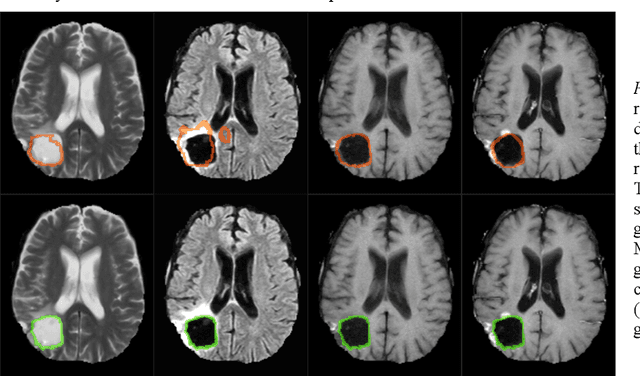

Abstract:In this work, we compare five deep learning solutions to automatically segment the resection cavity in postoperative MRI. The proposed methods are based on the same 3D U-Net architecture. We use a dataset of postoperative MRI volumes, each including four MRI sequences and the ground truth of the corresponding resection cavity. Four solutions are trained with a different MRI sequence. Besides, a method designed with all the available sequences is also presented. Our experiments show that the method trained only with the T1 weighted contrast-enhanced MRI sequence achieves the best results, with a median DICE index of 0.81.